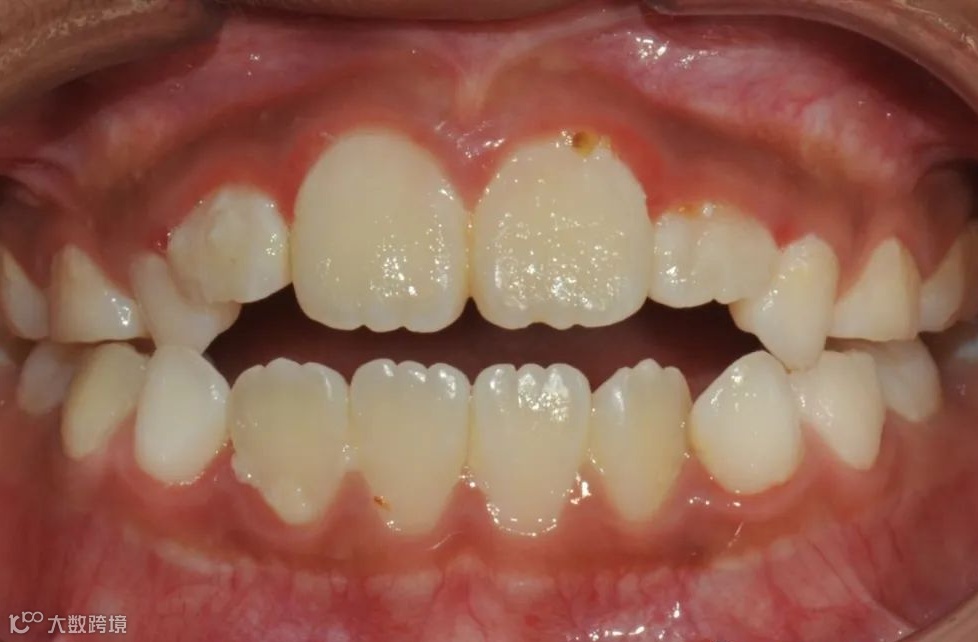

替牙期牙性反𬌗治疗前

替牙期牙性反𬌗治疗后